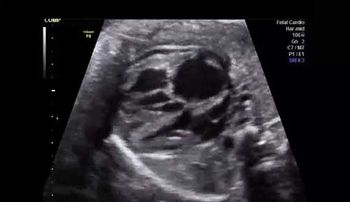

Challenge your diagnostic skills with this image of a fetal head.

Challenge your diagnostic skills: See anything out of the ordinary in this second trimester fetal heart study?